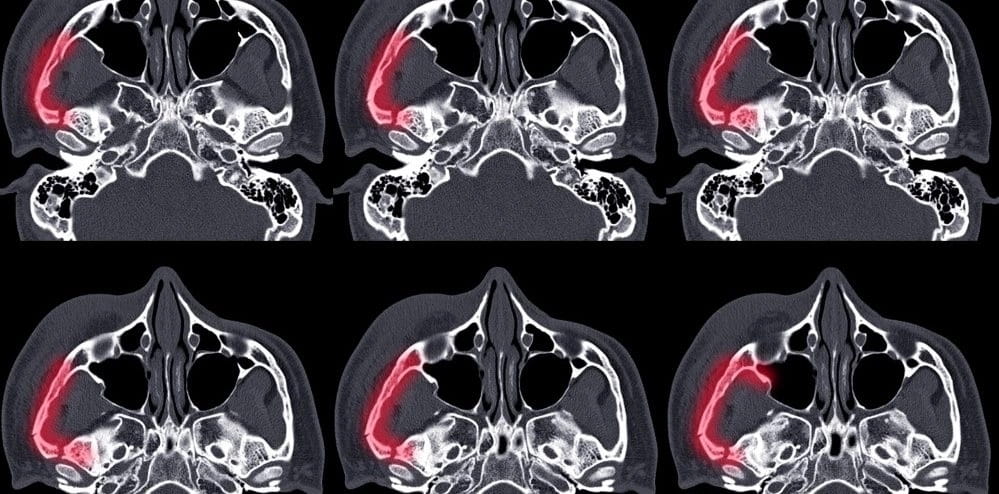

Чаще всего причиной головной боли при наклоне бывает гайморит (его еще называют синуситом). При этом заболевании болит голова в области глазниц, скул, щек, могут болеть зубы, и боль эта усугубляется именно при наклоне. Как распознать причину головной боли при наклоне и как ее лечить?

Синусит (гайморит) - общее название воспаления околоносовых пазух. Точнее, воспаление верхнечелюстной пазухи (гайморит), лобной пазухи (фронтит), решетчатой пазухи, клиновидной пазухи (сфеноидит). Последнее заболевание - сфеноидит - встречается крайне редко. И для всех этих заболеваний характерен общий симптом – сильная головная боль при наклоне.

Гайморитная головная боль при наклоне может быть вызвана перегрузкой пазух носа и воспалением, которое называется синуситом или гайморитом. Гайморит, в свою очередь, вызван респираторными инфекциями, такими как простуда или грипп, аллергией либо сенной лихорадкой.

В пазухах носа идет процесс воспаления, выделяются продукты распада (гной). Так как оттока из пазухи носа нет, продукты распада находятся в ней под давлением и усиленно всасываются в кровь, отравляя весь организм. Кроме того, избыточное давление раздражает синус стенки носа. Отсюда и характерные симптомы, в частности, сильная головная боль при наклоне головы.

Боль головы при гайморите чаще всего глубокая, пульсирующая, она сосредотачивается в передней части головы и лица.

Синусовые (гайморитные) головные боли часто начинаются, как только вы встаете утром, они могут усугубляться во второй половине дня. Гайморитная головная боль может трудно диагностироваться, по причине того, что ее симптомы похожи на головные боли напряжения и мигрени.

Головные боли при гайморите, как правило, вызывают эти симптомы

- Давление и боль в одной конкретной области лица или головы (например, в области глазниц)

- Лицо чувствительно при ощупывании

- Боль усиливается при резких движениях головы и наклоне вперед

- Сильнее и резче боли утром, потому что слизь собирается в носовых пазухах всю ночь

- Резкие изменения температуры, когда человек выходит на мороз из теплой комнаты, усугубляют боль

- Головная боль часто начинается во время простуды или сразу после нее

Если доктор подозревает у вас хронический гайморит, вам может понадобиться рентген, компьютерная томография (КТ) или магнитно-резонансная томография (МРТ). Если врач подозревает аллергию, которая может быть причиной гайморита, вам может понадобиться тест на аллергию. Вам может понадобиться дополнительное направление к специалисту, известному как ухо-горло-нос (ЛОР) врач или врач-отоларинголог. Этот специалист может выполнить носовую эндоскопию с использованием оптоволоконной области, чтобы четко рассмотреть состояние пазух носа.